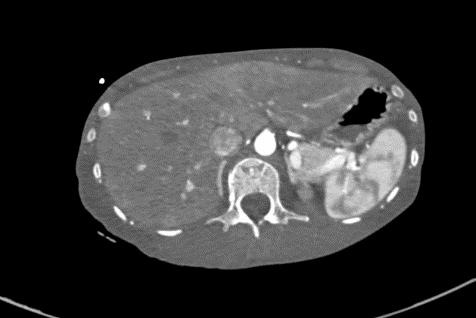

2021-4-29全腹增强CT:腹盆腔散在积液,上腹腔少量积气,腹壁软组织积气,盆腔置管影。肝实质灌注不均,肝内淋巴瘀滞,提示肝功能损害。右侧见一支副肾动脉;左肾动脉提前分支。双侧附件区见多房囊状低密度影,可见环状强化,囊肿?卵泡?或其它?

患者青年女性,慢性病程;主要表现为腹胀、呼吸困难,术后出现意识障碍、II型呼吸衰竭。经呼吸机辅助呼吸、对症支持等治疗后,患者意识恢复但呼吸困难无明显改善;既往有有粉尘接触史。查体见患者极度消瘦、营养不良,双肺呼吸音粗,可闻及散在湿啰音。血气示II型呼吸衰竭、高碳酸血症,轻度贫血,低蛋白血症,电解质紊乱,炎症指标、肌酶、BNP升高,院外腹水检查示漏出液,未见肿瘤细胞;胸部CT:双肺斑片影,抗感染治疗后病灶吸收;腹部增强CT:双侧附件区分别混杂密度团块影,内见多发囊泡影;心脏彩超:右心稍大,重度肺动脉高压。